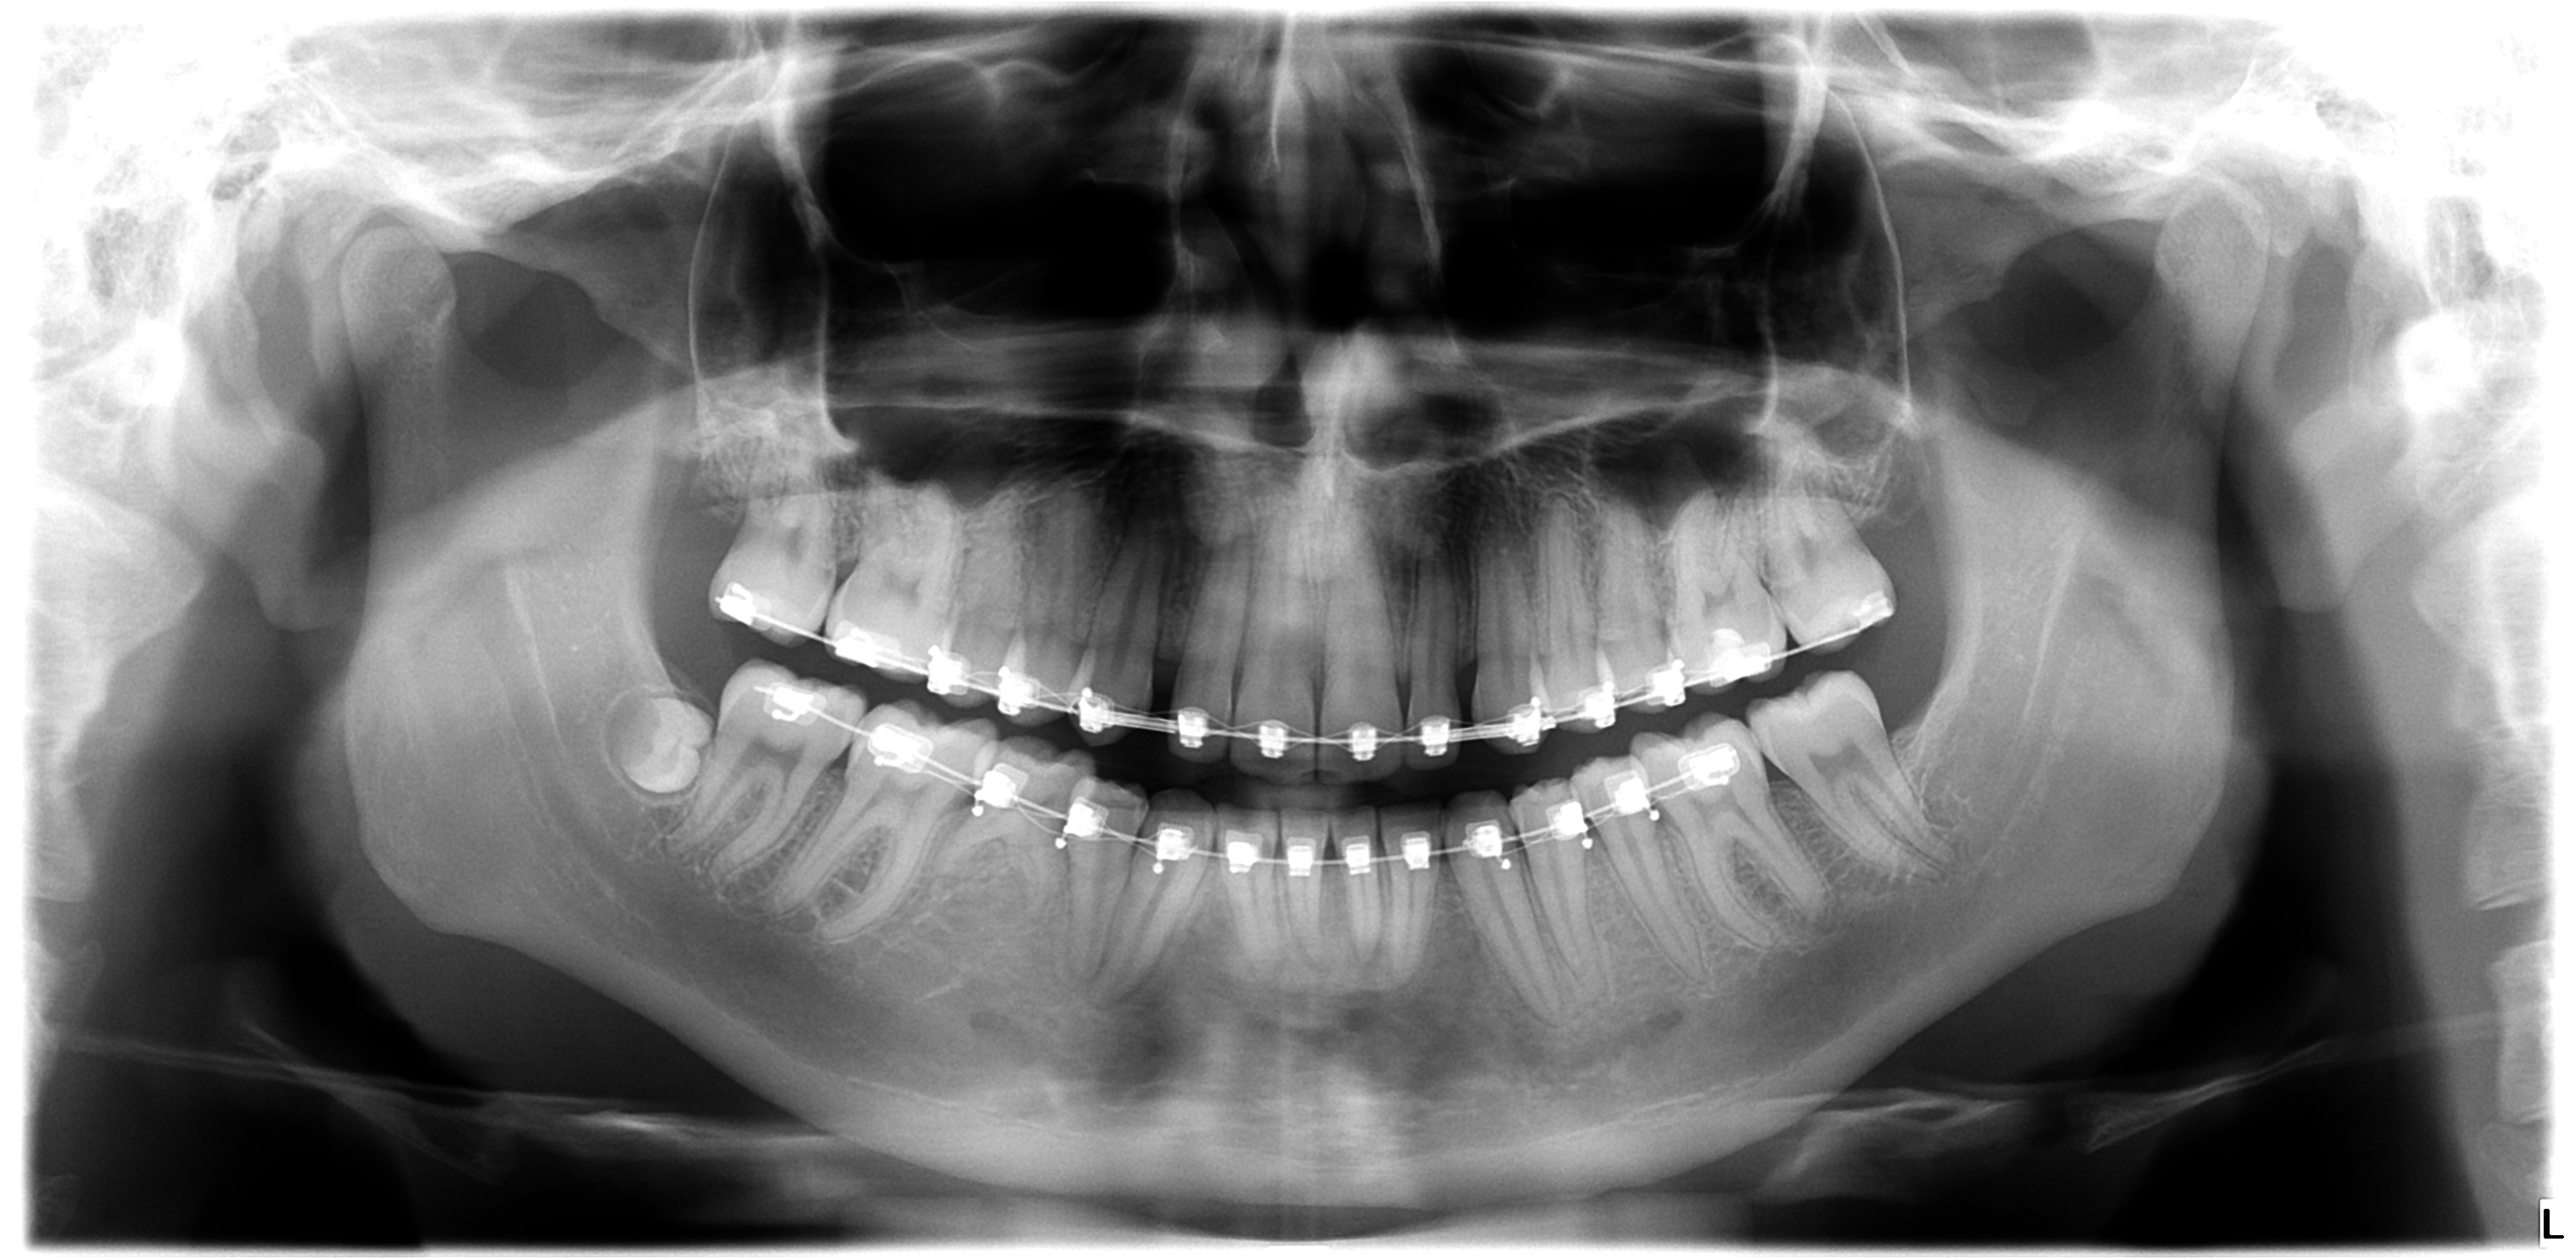

These are my CTs, how big do yall think i will ascend?

Before and after:

• Fabian_Noah_Luca_14012026_151449.png

Fabian_Noah_Luca_14012026_151449.png

2.5 MB · Views: 0